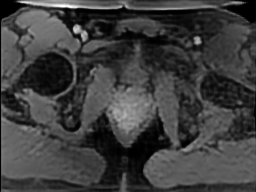

Tables 1 and 2 show our quantitative results: PSNR between the style (image we want to transfer style from) and generated image, SSIM and MS-SSIM between the content (image we want to take structure from) and generated image and finally, our proposed weighted SSIMs. For each style transfer direction and metric, our method consistently outperforms the other approaches. Figures 2 and 3 qualitatively highlight the good results of our method on 2D and 3D datasets. In addition, quantitative results on both figures show that our proposed metric preserves qualitative ordering of results for both style and content. In comparison, metrics such as SSIM struggle to accurately correlate to visual results.

Qualitative evaluation shows that the proposed method leads to sharper images, better content preservation, better localised CE and realistic MRI appearance. Quantitatively, we outperform the other algorithms with each metric, for each style transfer direction. While we expected that adding CE to images would be an easier task than removing CE, we found that for both tasks the method exhibits similarly performing quantitative and qualitative results. The results for style transfer with the kidney data show that when there is clear CE, it is easier to perform style transfer in both directions. However, when style transfer is performed on the prostate data, the model struggles in comparison to the kidney data. This may be due to the enhancement of the prostate being less defined than the kidney data. In figure 3(b), we can see the prostate with CE. Compared to figure 2(b) showing kidneys with CE, it is harder to determine the edges. The two original images shown in figures 3(a) and 3(b) are clear and easy to see some edges of prostate, in other images, it is harder to see the edges of the prostate.

(C) CW-SSIM: 0.39

(S) CW-SSIM: 0.29

(C) CW-SSIM: 0.53

(S) CW-SSIM: 0.31

(C) CW-SSIM: 0.42

(S) CW-SSIM: 0.54

(C) CW-SSIM: 0.93

(S) CW-SSIM: 0.62